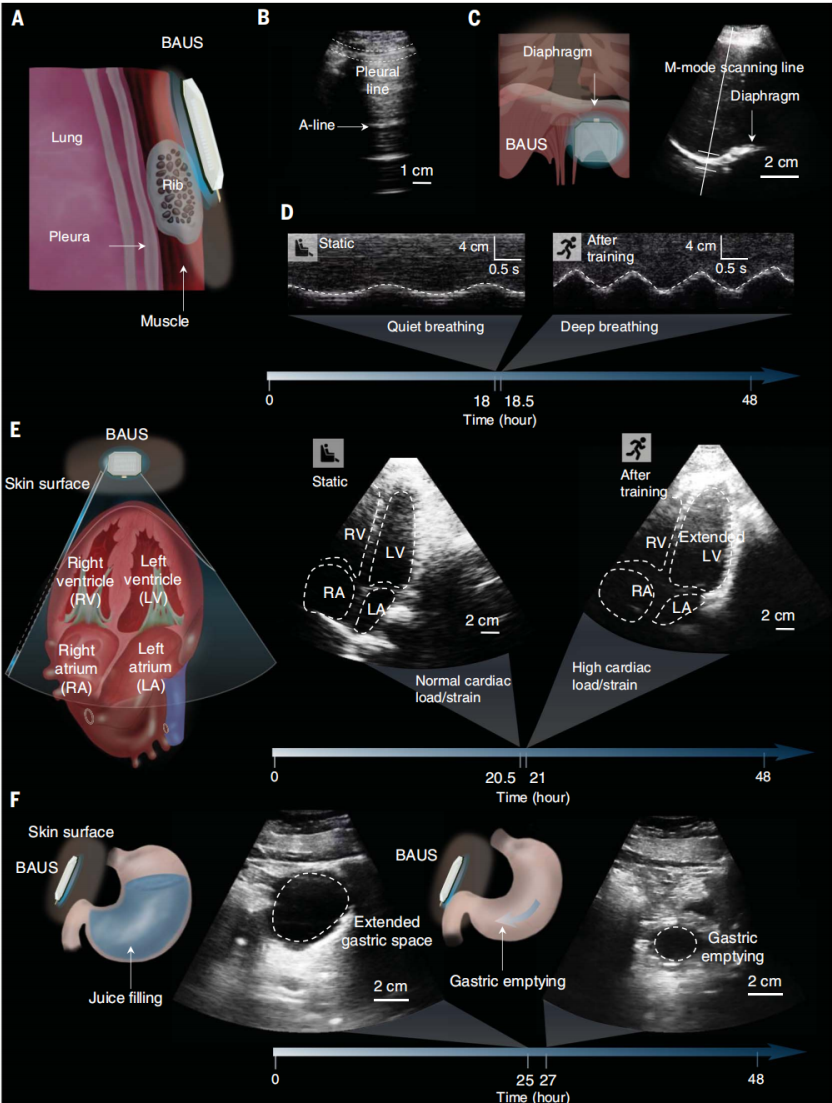

3.肺部疾病(例如COVID-19)监测:图4,A和B,以及图S33展示了粘附在受试者右胸(纵向)上的 3-MHz BAUS 相控阵设备获得的肺部成像结果(图4A)。BAUS系统可以提供48小时对肺部关键特征的连续成像,包括胸膜线和A线。BAUS 设备还能够连续稳定地对慢跑和骑自行车等身体运动下的肺进行成像。BAUS 成像显示受试者在48小时内有一条平滑的胸膜线和重复的A线,表明肺部健康、正常通气。尽管肺超声检查已被证明是诊断COVID-19患者的有效工具 ,但它主要在医院用于不频繁和不连续的肺部成像。相比之下,可穿戴BAUS系统可以在家中持续监测可能感染的COVID-19患者的症状。

4.运动状态监测:图4,C和D,展示了3-MHz BAUS相控阵设备在0.5小时体育锻炼前后粘附在受试者右前肋下区域获得的膈肌运动的成像结果。BAUS成像显示,相较于训练前的安静呼吸,训练后的横膈膜运动在幅度和频率上更加剧烈。

图4E 展示了附着在受试者左胸的3-MHz BAUS相控阵设备获得的心脏成像结果(通过心尖四腔视图可视化)。BAUS系统可以提供四个心腔动态的48小时连续成像:右心室、右心房、左心室和左心房。BAUS设备还能够连续稳定地对慢跑和骑自行车等身体运动下的心脏进行成像。例如,我们观察到在0.5小时的体育锻炼后,左心室的大小会显著增大。心脏腔室的连续图像可以进一步处理,以计算心脏应变的动态参数,这是指示心肌病的重要参数。

5.饮食监测:图4F展示了胃部成像结果,通过粘附在受试者上腹部皮肤上的3-MHz BAUS相控阵设备获得。BAUS成像系统提供胃窦横截面的48小时连续成像。例如,一旦受试者喝了450毫升果汁,我们观察到胃窦延长(图4F)。在接下来的2小时内,由于胃排空,胃窦横截面积逐渐减小(图4F)。